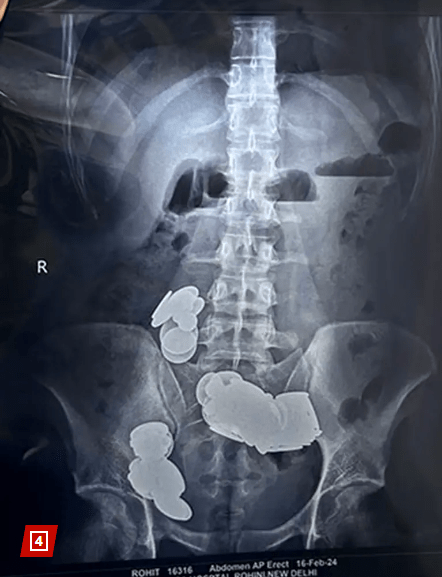

Οι ακτινογραφίες στις οποίες υπεβλήθη ο νεαρός άνδρας πριν από την επέμβαση έδειξαν ότι τα κέρματα και οι μαγνήτες είχαν προκαλέσει τέτοια εντερική απόφραξη στο σώμα του, που η άμεση χειρουργική επέμβαση για την αφαίρεση τους ήταν μονόδρομος.